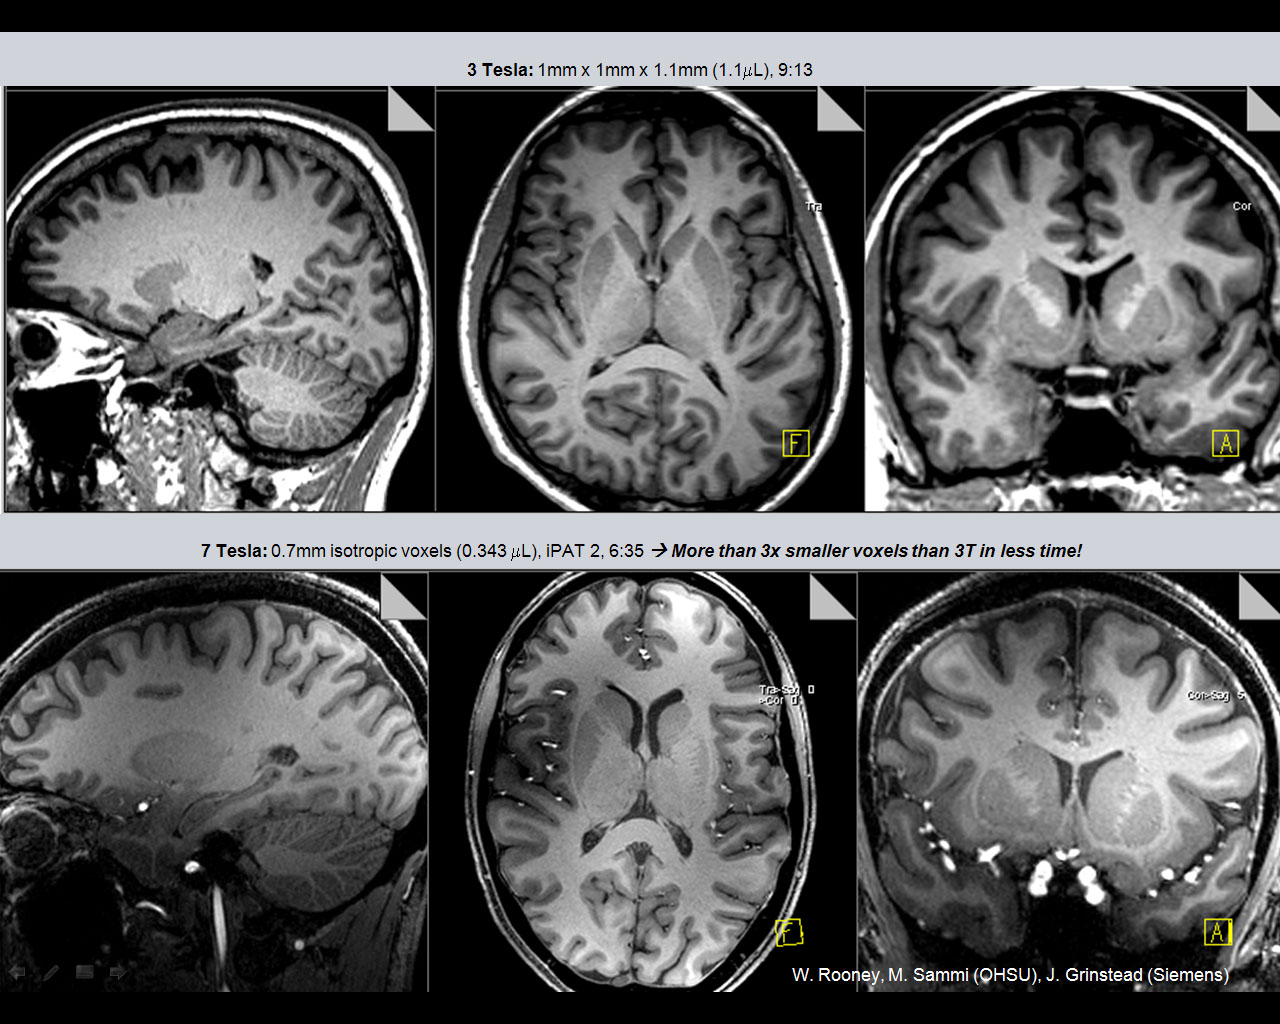

3 Tesla vs 7 Tesla

Comparison of 3 Tesla: 1mm x 1mm x 1.1mm (1.1µL), in time of 9:13min and 7 Tesla: 0.7mm isotropic voxels (0.343 µL), iPAT 2, in time 6:35min.  More than 3x smaller voxels in less time! W. Rooney, M. Sammi (OHSU), J. Grinstead (Siemens)